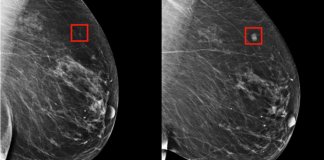

Com inteligência artificial, câncer de mama pode ser previsto cinco anos...

Eles desenvolveram um modelo para prever o câncer de mama até cinco anos antes de ele se manifestar. Mais um motivo para celebrar e incentivar o desenvolvimento científico e tecnológico.